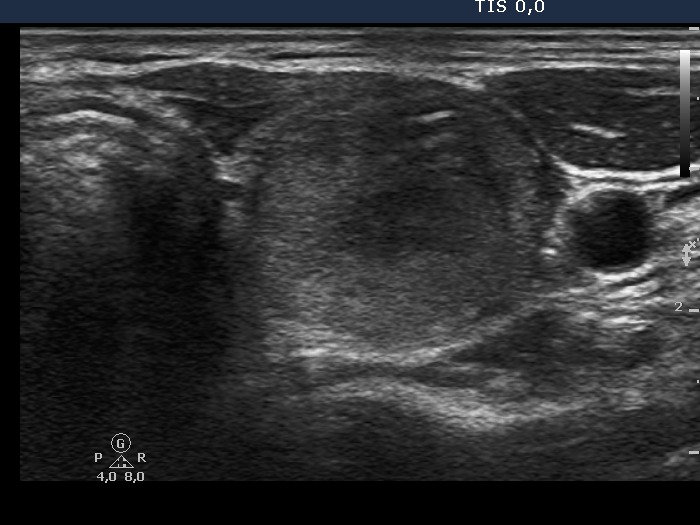

Papillary carcinoma - Case 1. |

Clinical data: a 47-year-old woman was referred for an evaluation of a nodular goiter which was discovered by the patient herself.

Palpation: a moderately firm nodule in the left lobe.

Functional state: euthyroidism (TSH-level 1.17 mIU/L).

Ultrasonography: the thyroids were echonormal. There were several insignificant lesions in the right while two nodules in the left lobe. One of the latter was echonormal and presented a halo sign and perinodular blood flow. The other nodule was hypoechogenic, inhomogeneous and contained microcalcifications.

Cytological diagnosis (from the hypoechogenic nodule): papillary cancer.

Histopathology: papillary cancer based on the nodule aspirated and normofollicular adenoma according to the echonormal nodule. There were metastatic foci in the right lobe and in several lymph nodes in the left side of the neck.